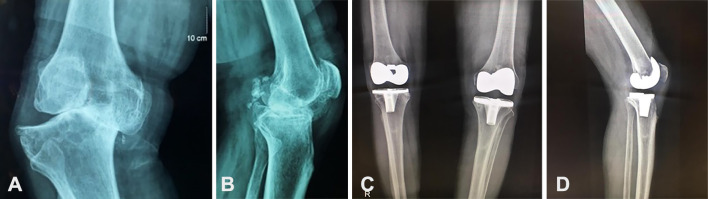

Results: 91 knees in 72 patients at 65.99±8.66 years of age and 8.28±2.58 years follow-up were studied. The tibial defects were managed with extra tibial cuts and adjustment of tibial component position in all, and the addition of structural autograft in 14 knees. 89 (98%) knees survived with a knee society score (KSS) of 79.4±17.6 and were significantly functioning well (P<0.001). Two knees required revision surgery. Significant improvement in outcome measurements was seen in all cases (P<0.001). No radiographic loosening, alignment change, or clinical instability was detected. The tibial plateau reconstruction without bone grafting and the ones that had autologous bone grafting had similar functional results and radiographic outcomes.

Conclusion: TKA with tibial defects of 15-25 mm treated with a semi-constrained posterior-cruciate ligament (PCL) sacrificing condylar prosthesis without any metal wedges or stem extensions with or without additional autogenous bone graft obtained very good functional and radiographic outcome and 97% survival in 6-17 years follow-up.